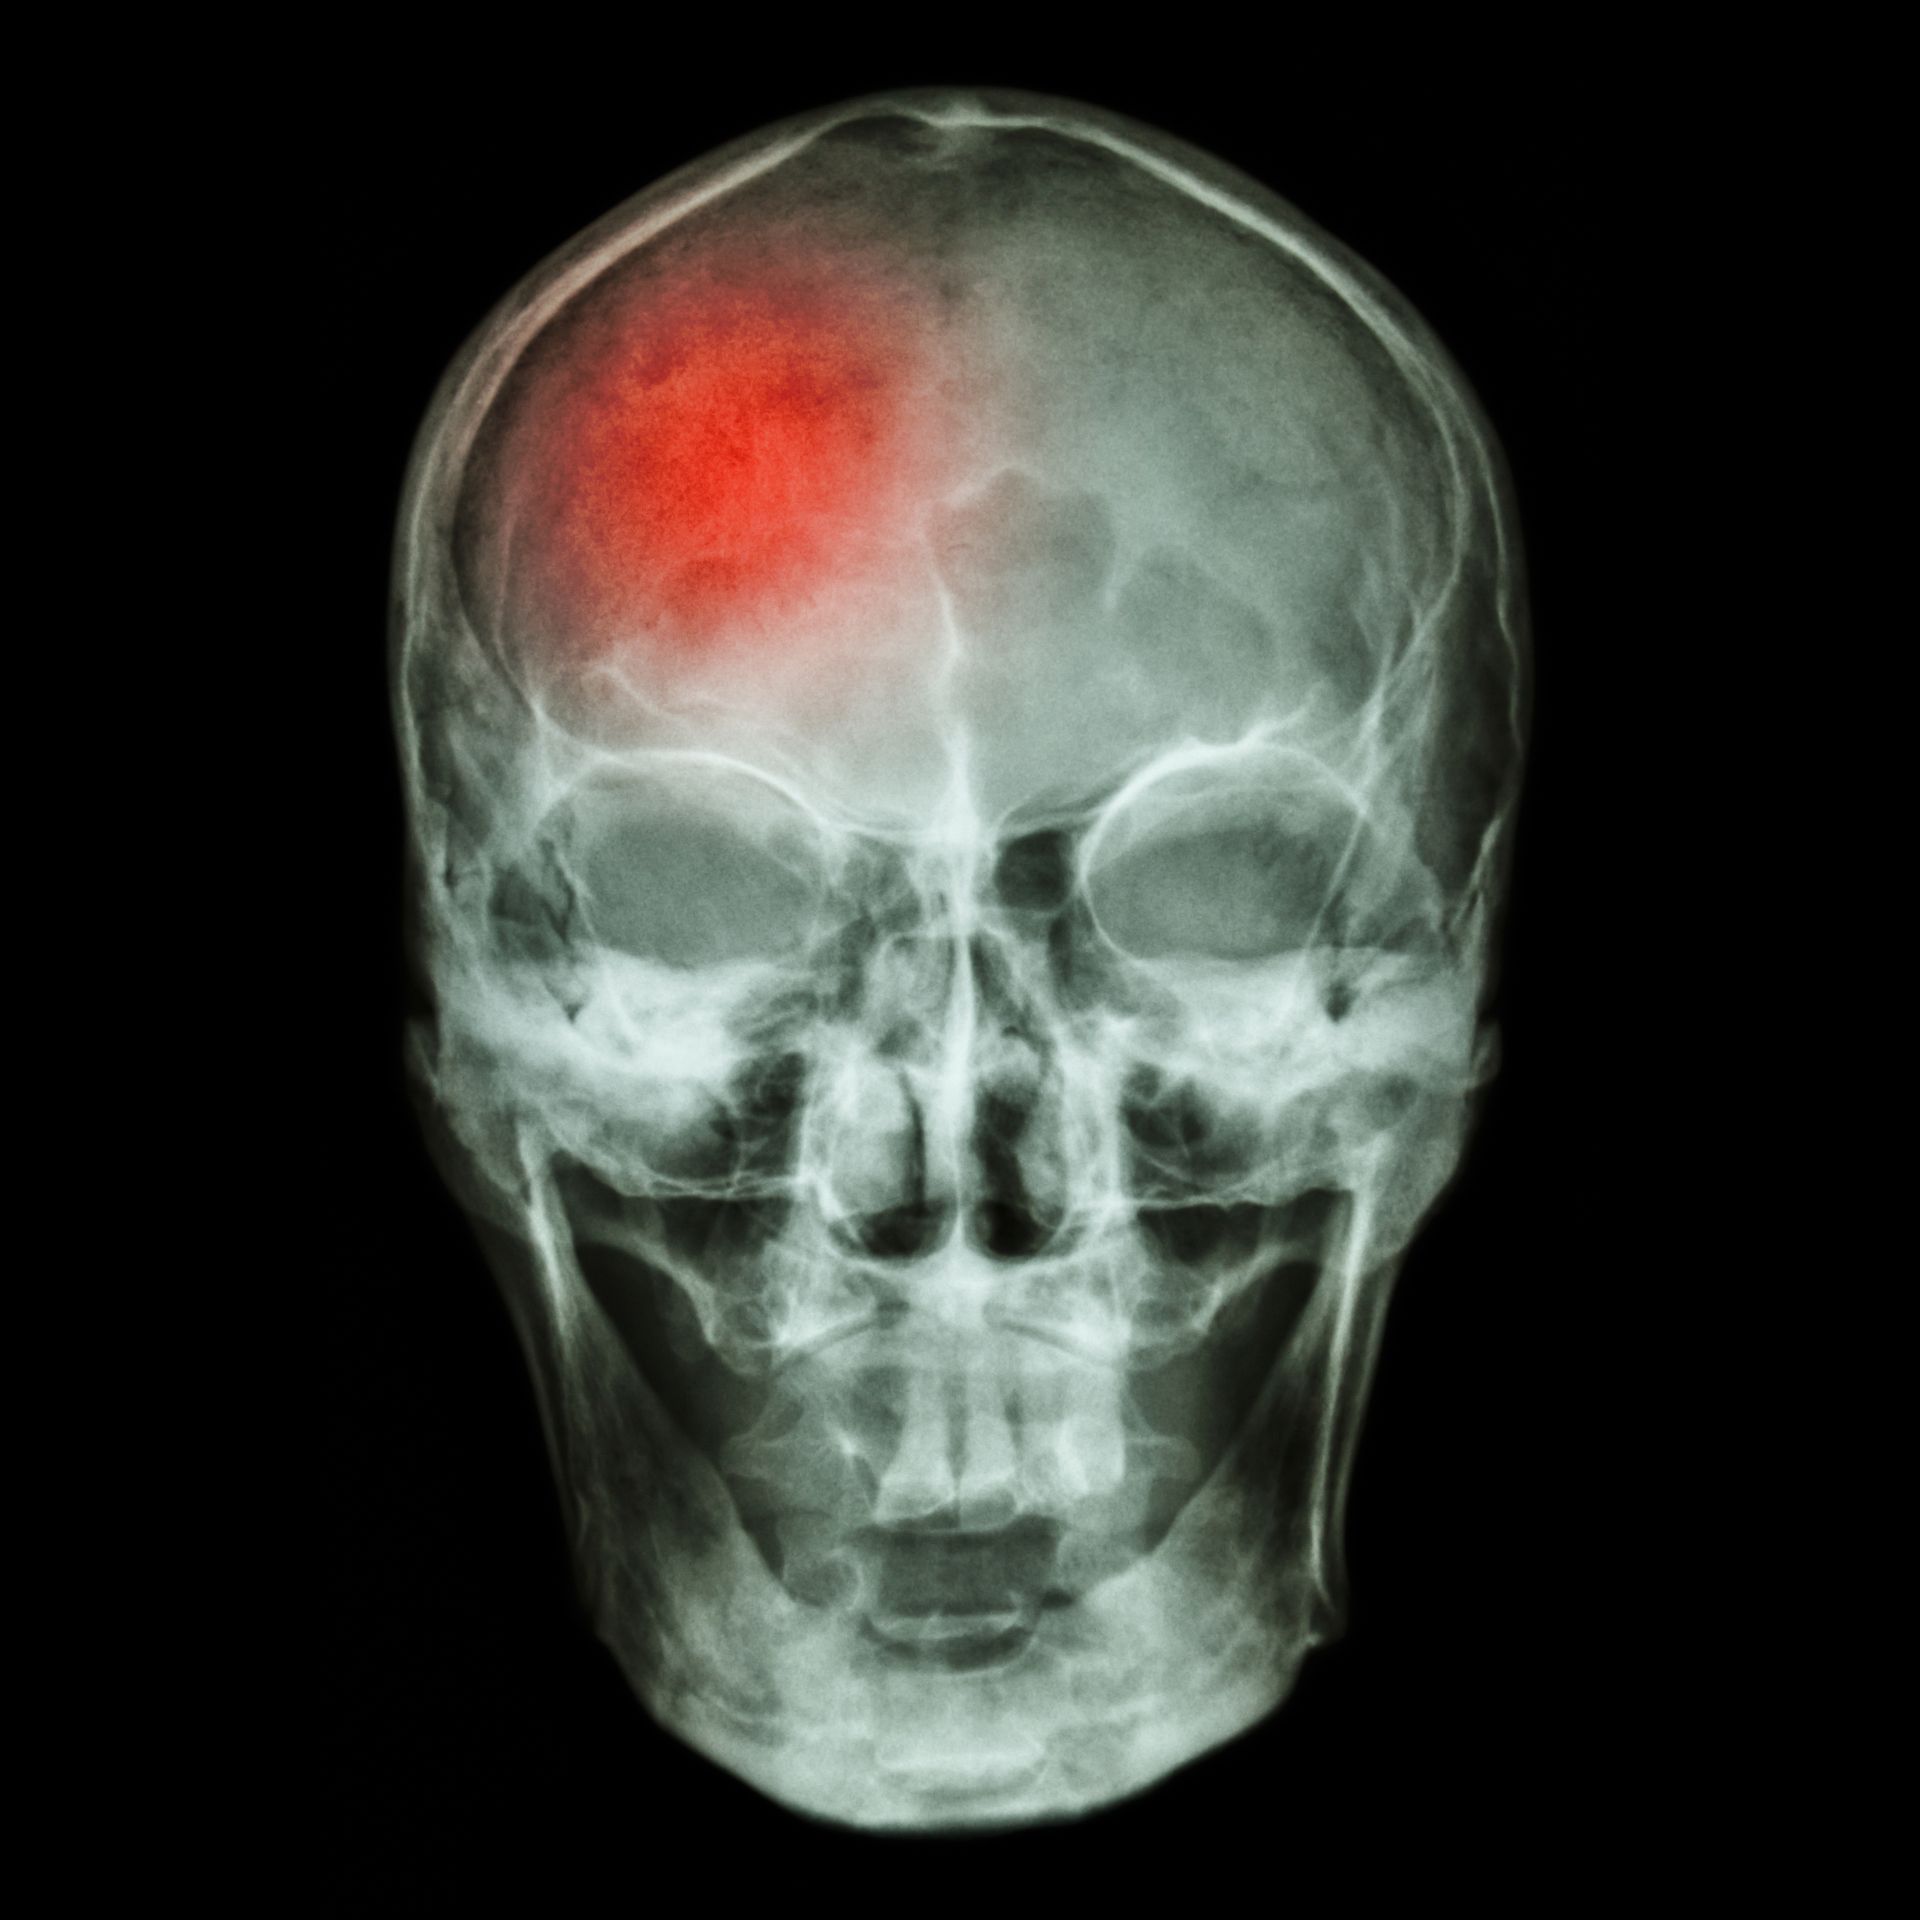

Luultua useampi aivohalvauspotilas sairastaa myös eteisvärinää

Eteisvärinä saattaa olla tiedettyä yleisempi vaiva aivohalvaukseen sairastuneilla, tuore tutkimus osoittaa. Uusi eteisvärinä todetaan joka neljännellä aivohalvauspotilaalla.

Nyt julkaistut havainnot perustuvat 50 tutkimuksen ja 12 000 aivohalvauspotilaan aineistoihin. Aineistojen avulla tutkijat selvittivät, kuinka monella potilaista todettiin eteisvärinä ensimmäistä kertaa vasta aivohalvaukseen sairastumisen jälkeen.

Uusia eteisvärinöitä diagnosoitiin jo heti sairaalahoidon aikana, mutta etenkin kotiutumisen jälkeen. Yhteensä uusi eteisvärinä todettiin lähes joka neljännellä potilaalla, tulokset osoittivat.

Tulostensa perusteella tutkijat uskovat, että eteisvärinä on yleisempi sairaus aivohalvauspotilailla kuin on uskottu. Näin ollen nykyistä useammat potilaat voisivat myös hyötyä hyytymisenestolääkkeistä ja siten todennäköisemmin välttyä uudelta aivohalvaukselta.

Eteisvärinä on yleisin rytmihäiriöistä ja sitä potee joka kymmenes yli 65-vuotias. Eteisvärinä aiheuttaa muun muassa sydämen tykytystä, hengenahdistusta ja väsymystä ja altistaa aivohalvauksille.